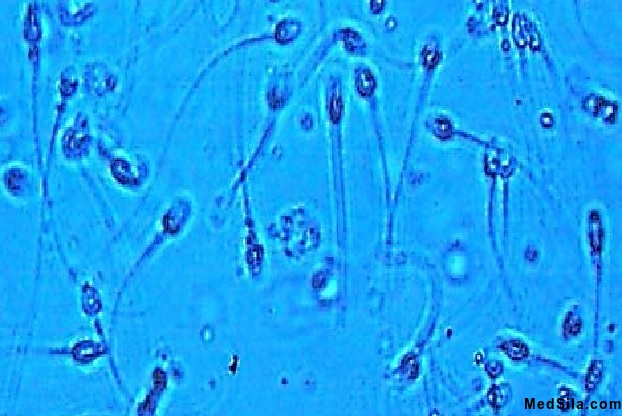

Сперматозоиды под микроскопом

3. Общее количество сперматозоидов в эякуляте (сперме) не менее 40 млн. Количество сперматозоидов в 1 мл. – до 20 млн/мл. После оценки общих параметров врач лабораторной диагностики проводит микроскопическое исследование (под микроскопом). Под объективом микроскопа врач – лаборант оценивает подвижность сперматозоидов (оценивается быстрота поступательных движений), форму сперматозоидов (наличие всех частей у активного сперматозоида - головки, шейки (средняя часть), хвоста), жизнеспособность (наличие незначительного количества мертвых сперматозоидов может носить временных характер, например, при тяжелых отравлениях), наличие склеенных (агглютинированных) сперматозоидов (в норме их быть не должно, иногда встречается при иммунной патологии).